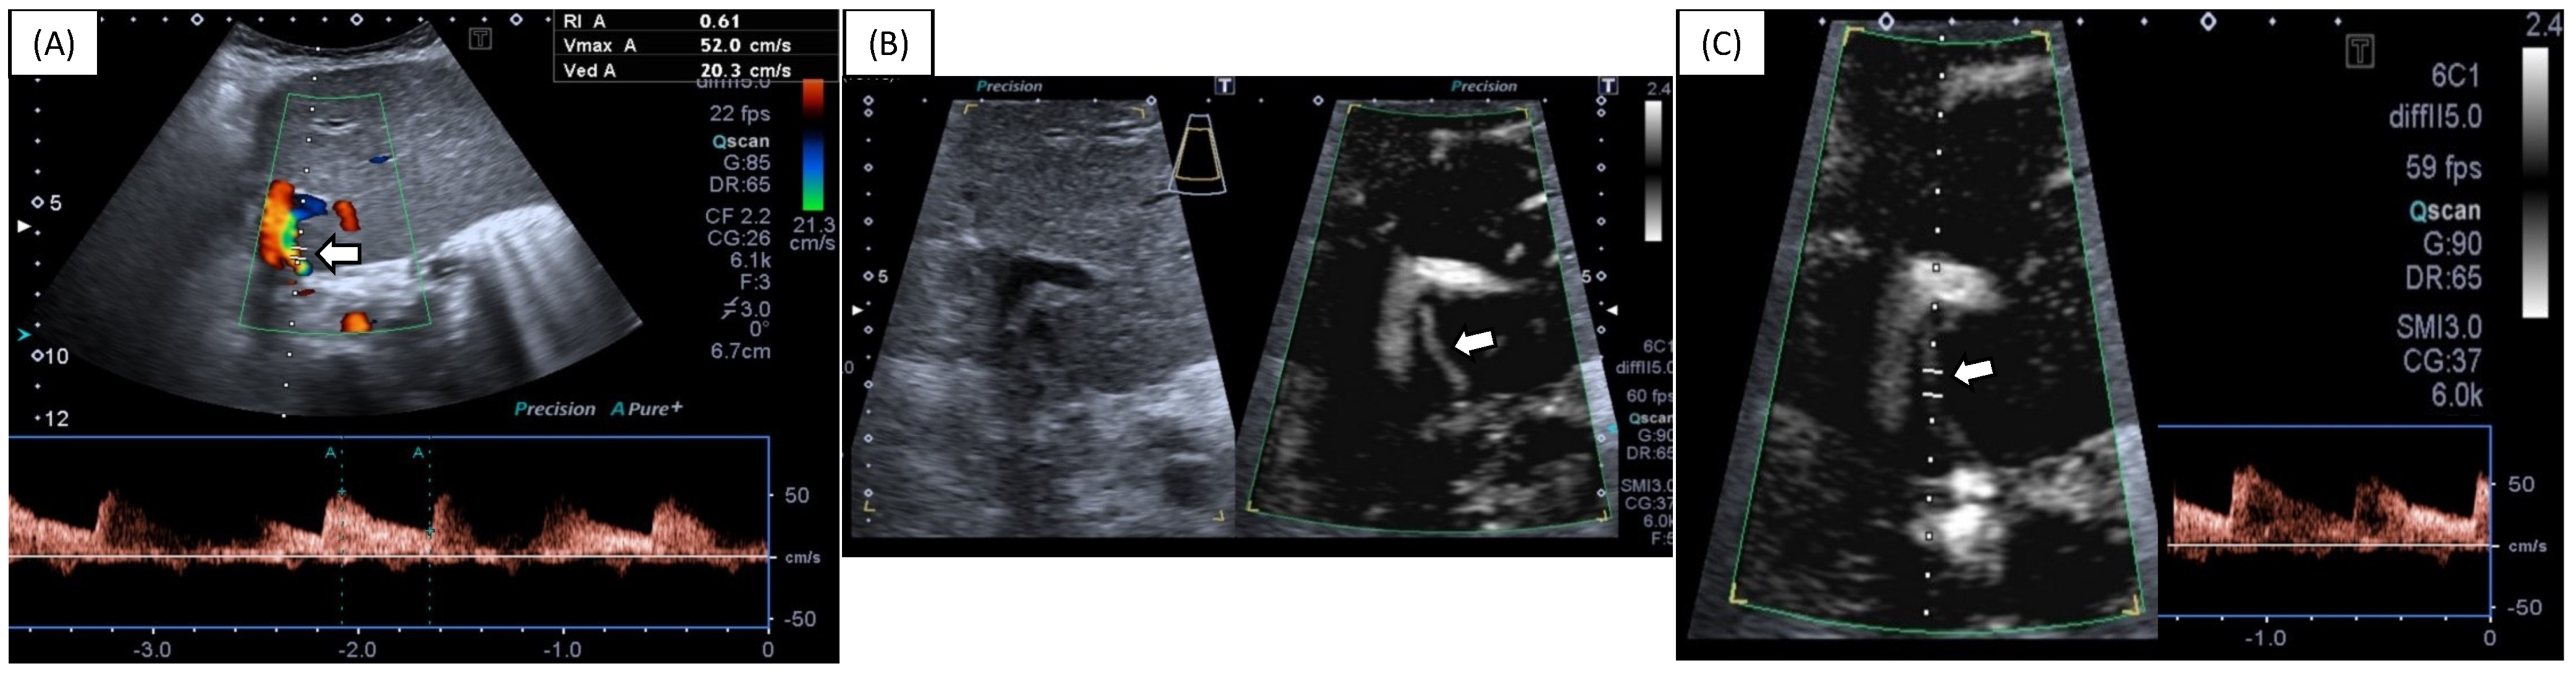

Superb Microvascular Imaging (SMI) Compared with Color Doppler Ultrasound for the Assessment of Hepatic Artery in Pediatric Liver Transplants: A Feasibility Study

- Gu, L.H.; Fang, H.; Liu, X.S.; Xia, Q.; Li, F.H. Additional value of superb microvascular imaging for assessing hepatic arterial blood flow after pediatric liver transplantation. Pediatr. Transplant. 2020, 24, e13785. [Google Scholar] [CrossRef]

- Jang, H.Y.; Kim, K.W.; Kim, S.Y.; Kim, J.S.; Choi, S.H.; Kim, S.Y.; Lee, S.G. Visibility of the graft hepatic artery using superb microvascular imaging in liver transplantation recipients: Initial experience. Acta Radiol. 2018, 59, 1326–1335. [Google Scholar] [CrossRef] [PubMed]